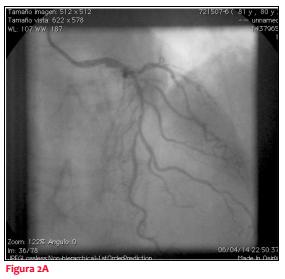

Se realizó CACG que evidenció arterias coronarias severamente calcificadas, lesiones severas en tercio medio de descendente anterior y ectasia de coronaria derecha dominante (figura 2A, y 2B).

Hemos presentado el caso de un paciente con síndrome coronario agudo con elevación transitoria del segmento ST, con cambios dinámicos electrocardiográficos dados por compromiso de distintos territorios coronarios y renivelación del segmento ST, que concomitantemente instala alergia cutánea y broncoespasmo. En este contexto se realiza una CACG que evidencia lesiones severas a nivel de la arteria descendente anterior. Con este resultado, y por la clínica que presentaba el paciente, con fuerte sospecha de vasoespasmo coronario, se decide diferir la conducta intervencionista, sujeta a la evolución del paciente.

Cuando se realiza nuevamente la CACG, a los tres días se evidencia lesión leve a nivel de la arteria descendente anterior, lo que confirma la naturaleza vasoespástica. Se ha definido la asociación de un síndrome coronario agudo en forma de angina inestable, vasoespástica e incluso infarto agudo de miocardio, desencadenado por la liberación de mediadores inflamatorios secundaria a un proceso alérgico, como síndrome de Kounis. Dado que el síndrome de Kounis es de diagnóstico clínico, creemos que nuestro paciente cumple con la definición. En nuestro medio existe el reporte de un solo caso(2). Como diagnóstico diferencial hemos planteado otras causas de síndrome coronario agudo con sobreelevación transitoria del ST y sin lesiones significativas en la CACG, como la angina variante de Prinzmetal y el vasoespasmo secundario a tóxicos (cocaína). En nuestro paciente descartamos el consumo de cocaína.